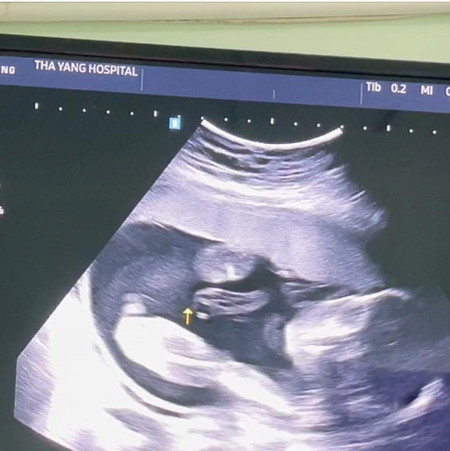

แบบนี้ได้ผู้หญิงหรือผู้ชายคะแม่ๆ🥰

ตอนลูกสาวคนที่2เห็นแบบนี้เลยค่ะ

เหมือนจะเป็นผู้หญิงนะคะ

น่าจะผู้หญิงค่ะแม่

ญ.ค่ะแม่🥰

เหมือนจะ ญ ค่า

หญิงค่าาา😅